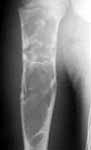

This 12 yr old boy was treated by me in May 2002 for pathological fracture right humerus conservatively. Curettage and bone grafting was suggested but parents were not willing. Xrays taken on 6th July 2002 shows the fracture united. He was protected by an Alkathin Brace for the Right Arm.

3-5-02